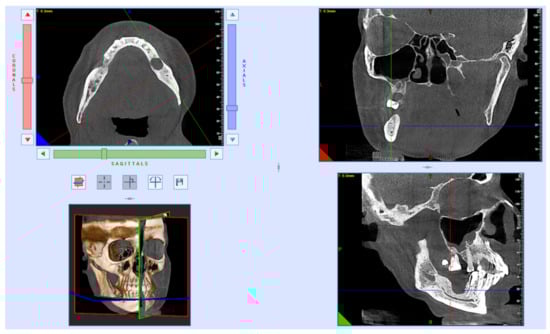

After 7 years, the bone reparation process had finished. Furthermore, the patient had dental implant placements. The loss of dental implants is not related to the fracture that occurred more than 7 years ago. Due to improper loading of the installed orthopedic structures, bone resorption occurred (Figure 5).

Figure 5.

CT scan after dental implant loss before bone plasty 7 years after surgery.

After removal of the dental implants that have undergone peri-implantitis, repeated CBCT examinations and prosthetics will be performed, considering the mechanical load and the peculiarities of the bite.